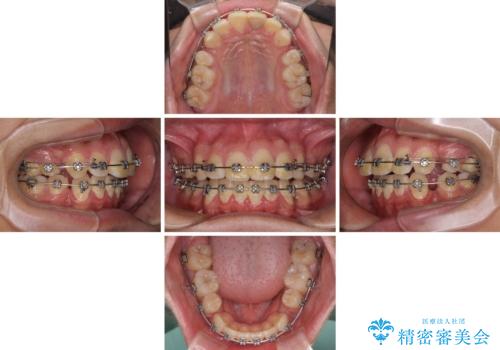

- 矯正装置

- メタルブラケット

- 治療期間

- 2年10ヶ月

小学生の頃に上顎前歯をぶつけ、歯の一部が破損している状態であったので、歯根が歯槽骨と癒着して移動しない可能性がありましたが、無事に治療を終えることができました。

受験勉強と重なり、舌のトレーニングが十分に行えず、高校生としてはやや長期間の治療となりました。